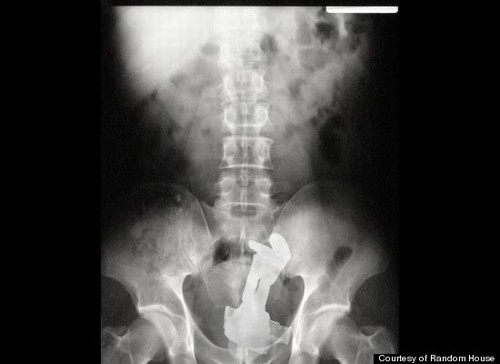

deveriam). A ideia partiu de três médicos norte-americanos, Rich Dreben, Murdoc

Knight e Marty Sindhian. Após ouvir centenas de relatos de pacientes que foram

parar no hospital com objetos estranhos entalados, os três doutores resolverem

fazer uma compilação de chapas de raio X.

Nas fotos há bonecas Barbie, garrafas, celulares,

tomadas, fitas cassete (nostálgico isso, não?) e até mesmo um cabide.

Mas o campeão de esquisitice foi mesmo o Buzz Lightyear, boneco da animação Toy Story.